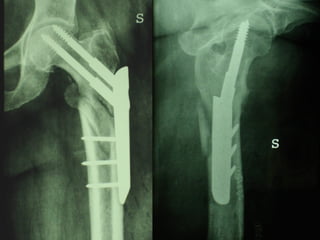

La placca a compressione percutanea (PC.C.P.) di Gotfried è un mezzo di sintesi studiato per assicurare un “impattamento controllato” delle fratture pertrocanteriche grazie alle due viti telescopiche prossimali che garantiscono una ottima stabilità rotazionale

Tradizionalmente si ritiene importante per la stabilità delle fratture pertrocanteriche l’integrità della parte mediale della metafisi prossimale del femore

In realtà la zona più importante per la ricostruzione di questo tipo di fratture è il muro laterale contro il quale si impatta il frammento metaepifisario mediale

Se il muro laterale è rotto o viene lesionato durante la sintesi , come spesso accade in fase di applicazione della vite cefalica dei chiodi endomidollari o della vite-placca, andremo incontro al collasso della frattura e ad un conseguente lungo periodo di impotenza funzionale

Con la placca di Gotfried non si è mai riscontrato un danno iatrogeno del muro laterale e nessun collasso della frattura.Ciò è dovuto al fatto che i fori per l’applicazione delle due viti prossimali sono di piccolo diametro (9 mm) rispetto ai 16-32 mm necessari per introdurre la vite cefalica di un chiodo endomidollare o di una vite-placca a compressione.

La placca PC.C.P. viene inoltre applicata per via percutanea attraverso due piccole incisioni ottenendo in tal modo un minimo trauma chirurgico ed una  perdita di sangue estremamente ridotta in pazienti che per l’età  sono già in condizioni  critiche

Dal Gennaio 2005 ad Agosto 2006 110  placche di Gotfried Età media  : 78 anni (range 29-94) Tempo chirurgico: 30 minuti (range 12-45) IMMEDIATA CONCESSIONE DEL CARICO